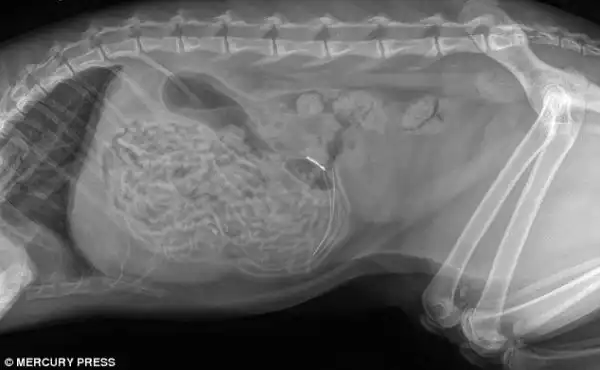

Врачи были очень удивлены, обнаружив большой кусок неизвестной массы в животе боксера

Как выяснилось, этой массой был огромный кусок клея, который по всей видимости собака стала есть в жидком состоянии, и который в последствии застыл у неё в животе